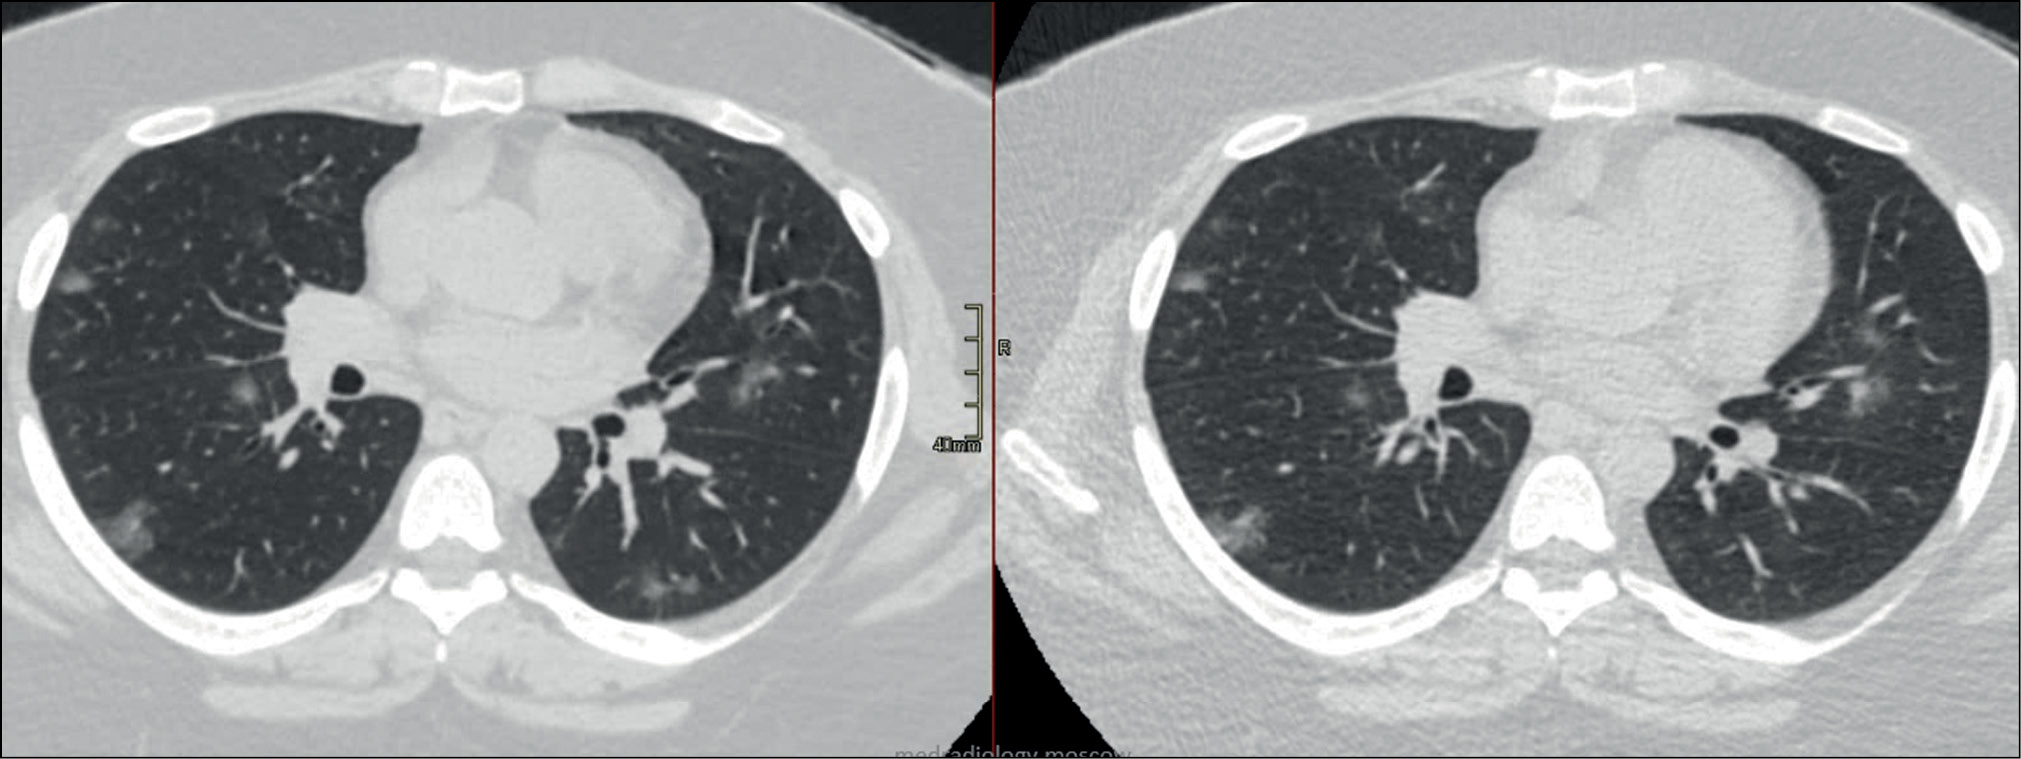

Interestingly, a parameter to be changed when optimizing the scanning protocol can be universal for various clinical tasks. Therefore, in LDCT for lung cancer screening, different groups of authors also changed the tube current [55, 56]. However, the development of a specialized LDCT protocol should be initiated with a study on a model object (phantom) to select the optimal method for reducing the exposure. For example, Gombolevsky et al. [57] developed the LDCT protocol for the diagnosis of COVID-19 using a phantom with thickening plates, while setting the automatic tube current control system (Sure Exposure 3D) to a sufficient level to detect ground-glass lesions with a maximum reduction in radiation exposure (SD = 36). A comparison of the protocol selected according to the results of the phantom study with standard CT and LDCT for lung cancer screening is shown in Fig. 1.

Figure 1. Comparison of a dedicated low-dose computed tomography protocol for COVID-19 (SD = 36) with standard and low-dose computed tomography for lung cancer screening. Data on radiation exposure and axial tomograms of the phantom at the level of the lower and middle zones of the lungs. Low-dose computed tomography for lung cancer screening was developed considering the need for radiation exposure limitation as preventive measures according to SanPin (disease control and prevention standards) and has the lowest signal-to-noise ratio. The proposed protocol for low-dose computed tomography for COVID-19 considers the densitometric characteristics of ground-glass lesions with a significant reduction in radiation exposure.